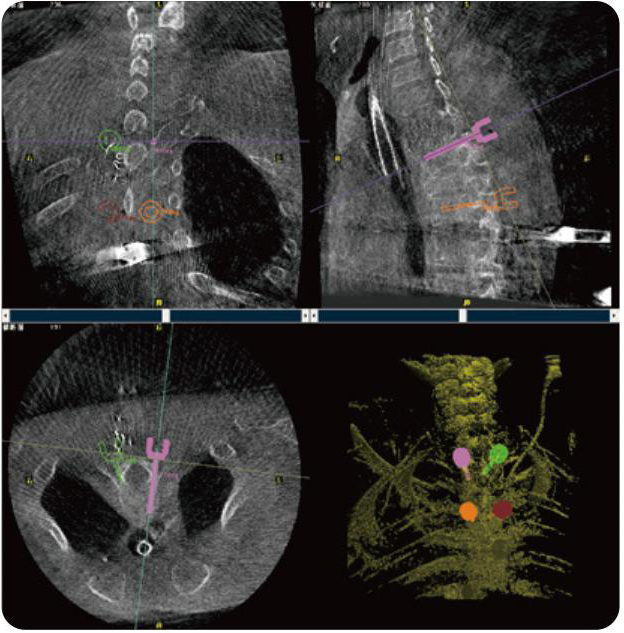

PL300B可應用于多節段脊柱外科手術,輔助醫生定位病灶部位,為脊柱外科手術(經皮椎體成形術、椎弓根螺釘內固定術等術式)提供術前手術流程規劃、入釘位置、角度可視化引導,模擬仿真入釘輔助。

PL300B搭配普愛醫療自主研發生產的平板3D C形臂,借助一體化自適應配準( 軌跡配準)技術,通過追蹤C形臂三維采集軌跡,自動完成圖像坐標建立和系統坐標配準。配準精度更高,操作步驟少,系統運作效率高。